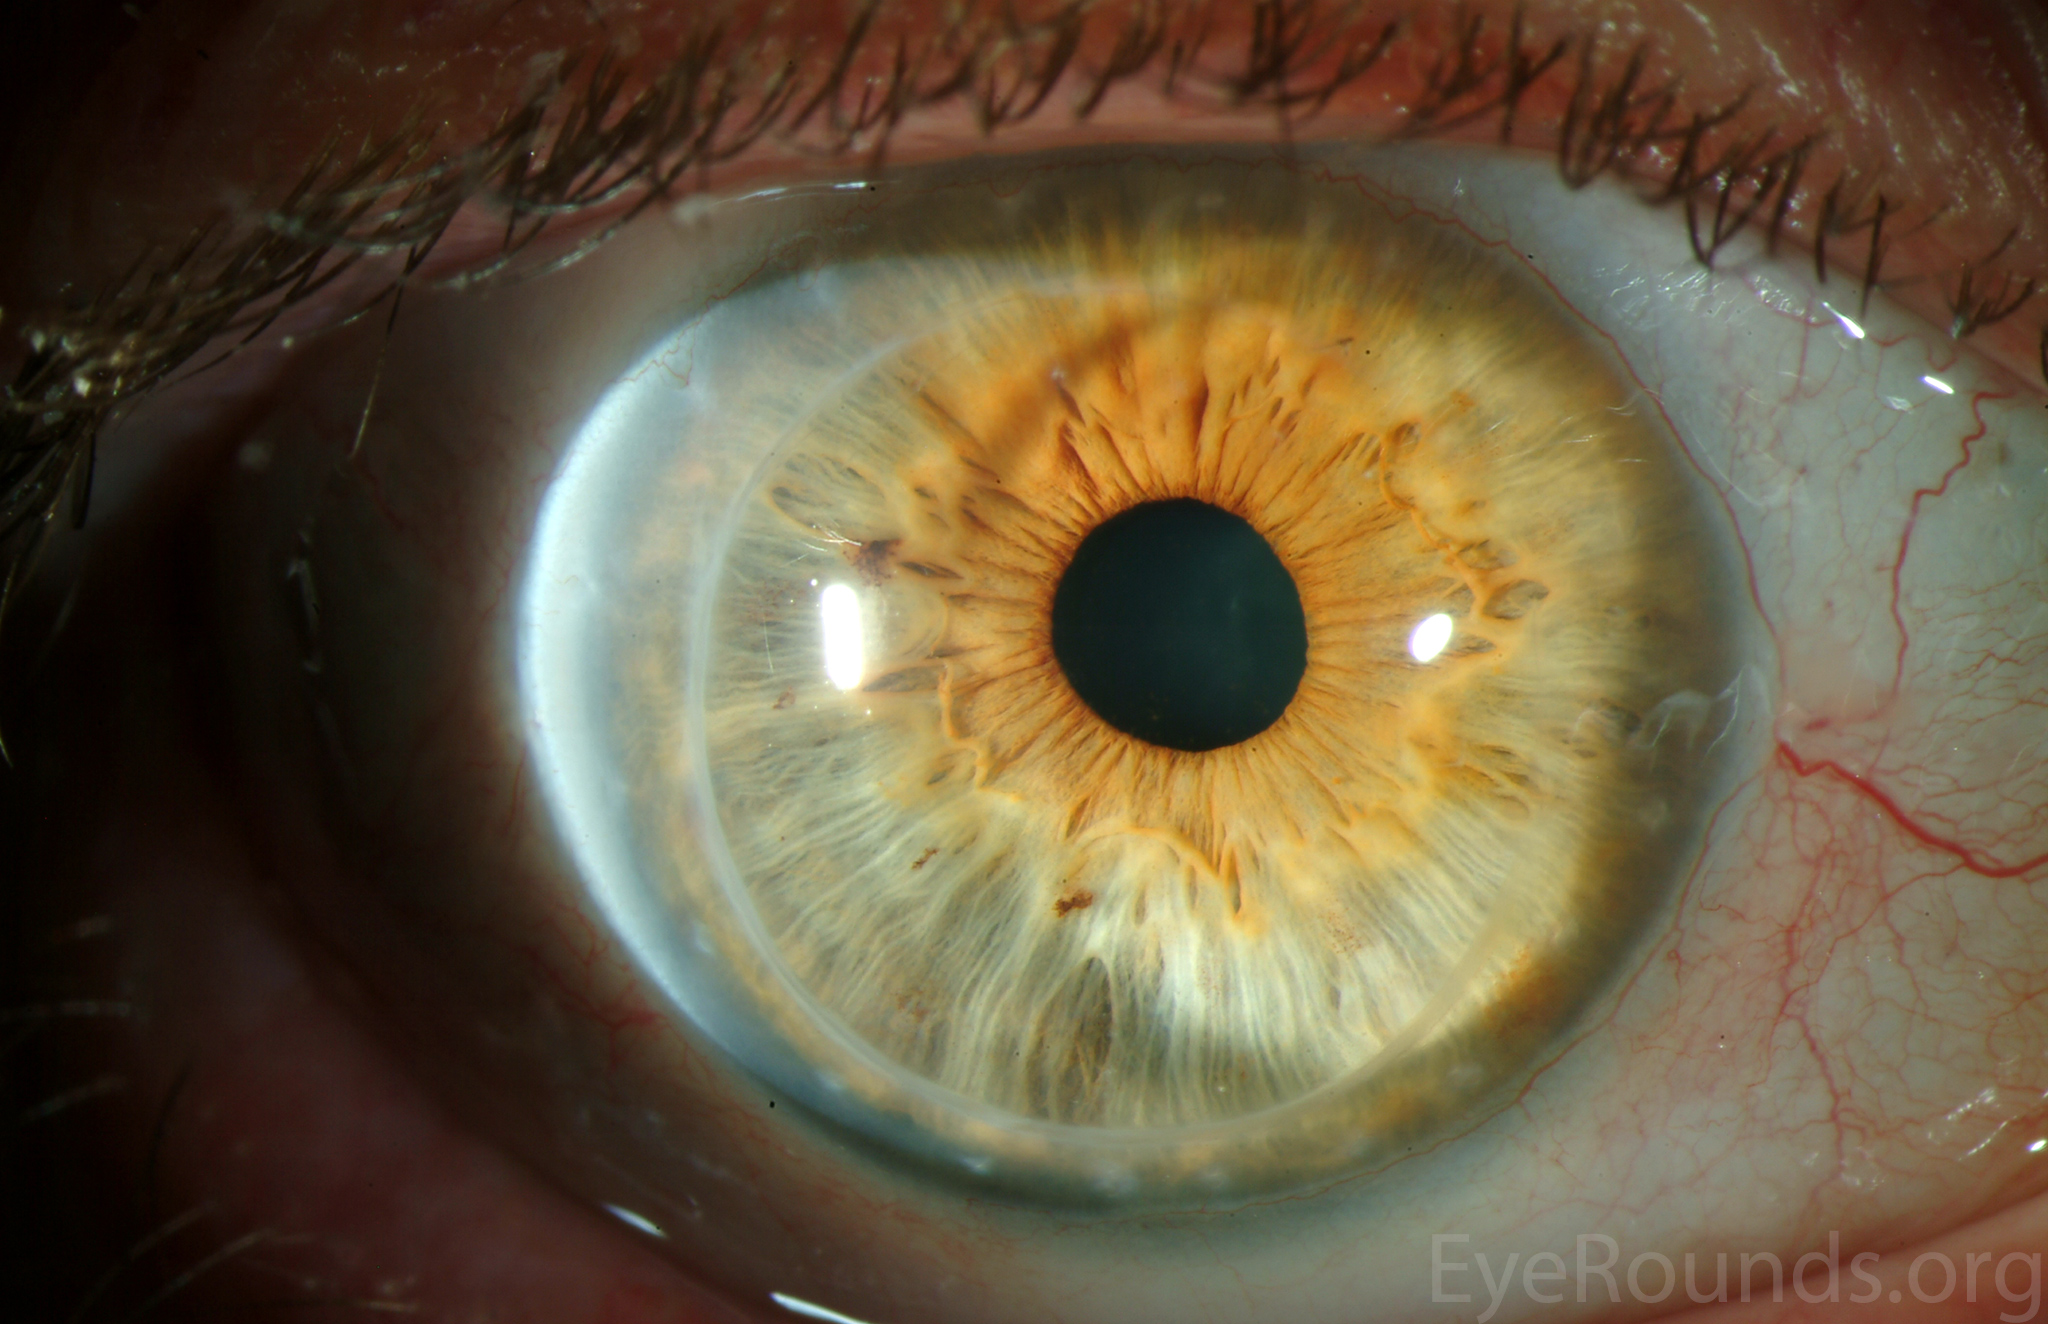

PK is a full-thickness transplant procedure, in which a trephine of an appropriate diameter is used to make a full-thickness resection of the patient's cornea, followed by placement of a full-thickness donor corneal graft. Interrupted and/or running sutures are placed in radial fashion at equal tension to minimize post-operative astigmatism (Figure 2). Later, the sutures are removed selectively to reduce the amount of astigmatism present. A transplant can last decades with proper care (Figure 3). While once the most prominent type of corneal transplant, PK has been supplanted by partial thickness techniques for endothelial dysfunction without significant stromal scarring. PKs are performed primarily for visually significant stromal scarring, opacities with an uncertain status of the endothelium or significant posterior corneal involvement, corneal ectasia (such as keratoconus and pellucid marginal degeneration, especially if there is history of hydrops), combined stromal and epithelial disease (such as Peters anomaly), and infectious or non-infectious corneal ulcerations or perforations (1, 14). A variant of the procedure, the mini-PK, can be used to treat more focal defects in the cornea (Figure 4).

DALK is a partial-thickness cornea transplant procedure that involves selective transplantation of the corneal stroma, leaving the native Descemet membrane and endothelium in place. A trephine of an appropriate diameter is used to make a partial-thickness incision into the patient's cornea, followed by pneumodissection or manual dissection of the anterior stroma. This is followed by placement of a graft prepared from a full-thickness punch in which the donor endothelium-Descemet membrane complex has been removed. The intention is to preserve the patient's Descemet membrane and endothelium. Similar to PK, the graft is secured with interrupted and/or running sutures (Figure 5) and these are then selectively removed post-operatively (Figure 6).

DALK is useful for processes involving the corneal stroma in the presence of healthy endothelium. Examples include corneal ectasia (such as keratoconus in the absence of hydrops), corneal scars that are not full-thickness, and corneal stromal dystrophies (1, 15, 16).